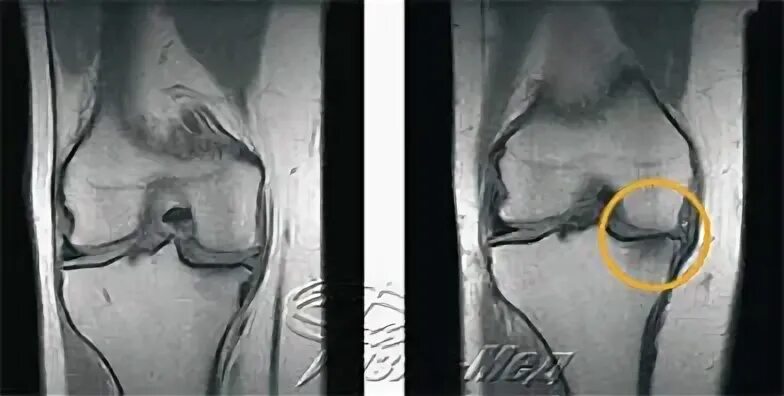

Мрт суставов кемерово